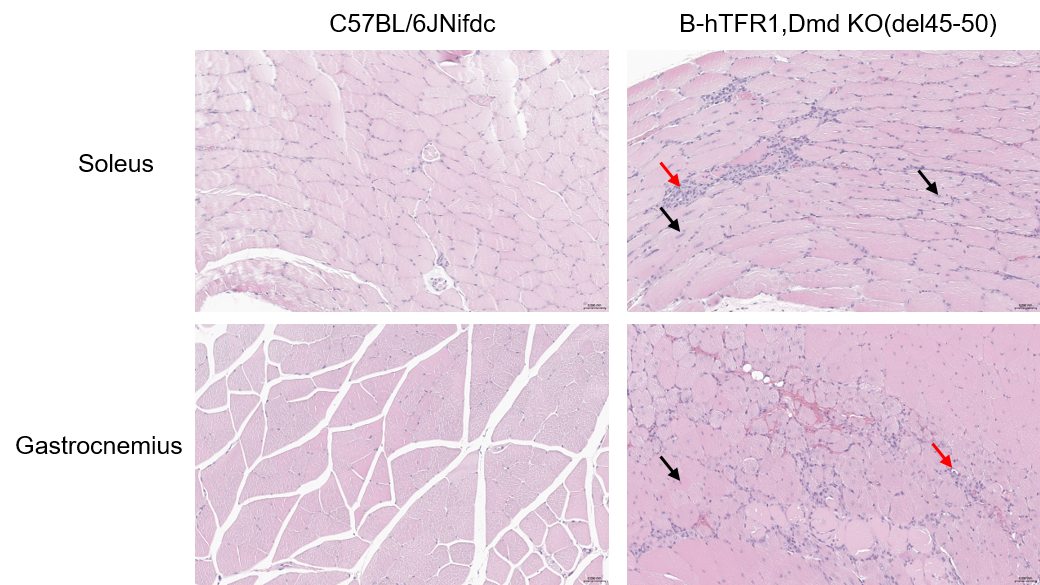

Representative histological images of skeletal muscle from wild-type C57BL/6JNifdc and homozygous B-hTFR1, Dmd KO(del45-50) mice. Gastrocnemius and soleus muscle sections from 3-month-old wild-type C57BL/6JNifdc and homozygous B-hTFR1, Dmd KO(del45-50) mice were presented to display histopathological phenotypes. Gastrocnemius and soleus muscle were stained with hematoxylin and eosin (H&E). Tissue histology was normal for wild-type control mice, but the muscle from homozygous B-hTFR1, Dmd KO(del45-50) mice displayed inflammation (red arrow) and centrally-located nuclei (black arrow).